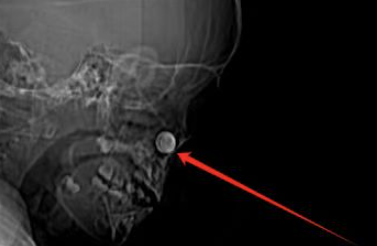

▲男童的鼻腔内有一颗纽扣电池。院方提供

5月22日,医生从男童左边鼻腔内取出一个指甲大小的纽扣电池。由于电池在鼻腔内停留时间过久,孩子已经患上了鼻窦炎。另外,电池产生的化学反应严重腐蚀鼻腔黏膜,导致鼻中隔软骨出现坏死、穿孔,鼻梁也出现了塌陷。

▲医生从男童左边鼻腔内取出一个纽扣电池。院方提供